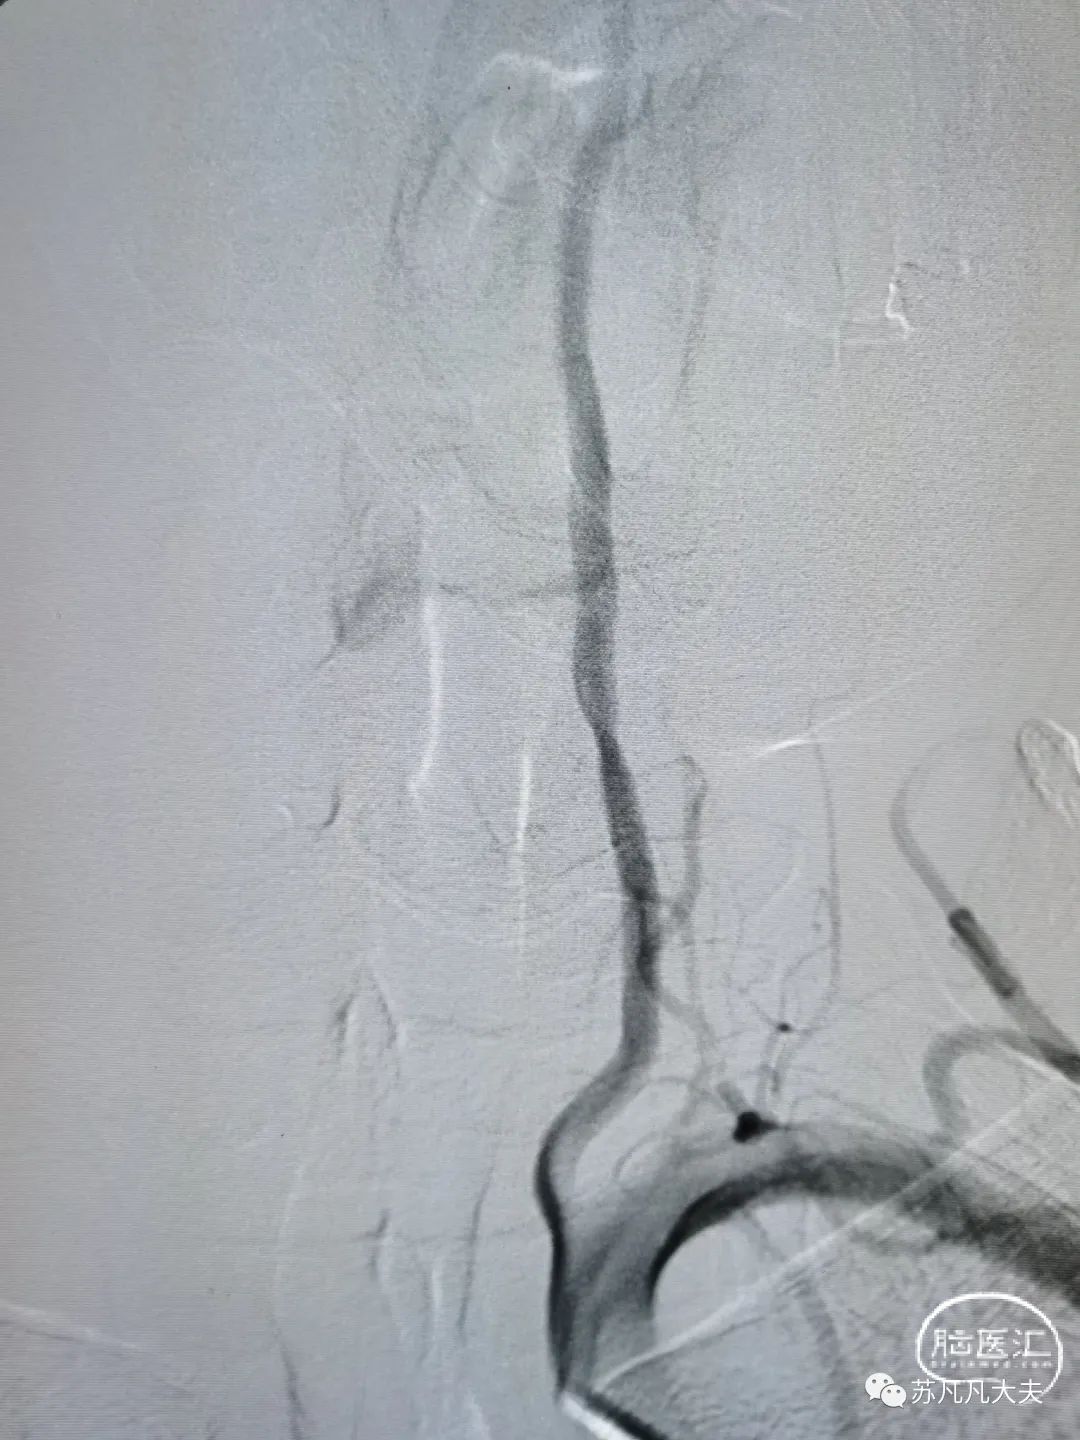

DSA示右椎发育不良,颅内段闭塞